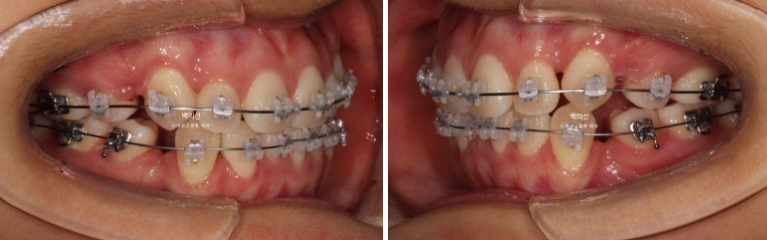

중심선은 잘 맞습니다.

어금니 교합 관계는 1급이고 물샐틈 없네요